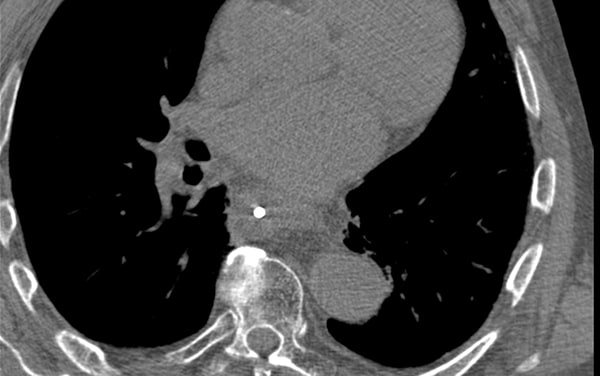

对于支气管和食道癌,此步骤并非必要步骤。在某些情况下,需要进行CT成像,用于制定治疗计划。对于食道癌,这可能是一个标准计划。

CT成像